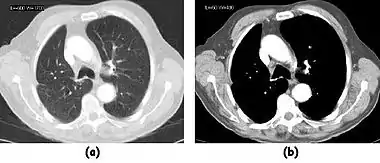

- A choice of filters can generally be selected to enhance either soft tissue features in the image or bone detail. Indeed, the image can be post-processed using a different filter after the scan has been completed if needed. Images can be generated to enhance bone detail or display subtle low contrast masses without the need to re-scan the patient. The filter choice therefore has a major impact on image quality. The two most common filters used in X-ray CT are those due to Ramachandran & Lakshminarayana (commonly called the Ram-Lak) and Shepp & Logan. Viewed in spatial frequency space, the former is essentially a ramp filter with a cut off frequency and the latter combines a smoothing filter with the ramp to attenuate high frequency noise. The ramp filter compensates for the artefacts introduced by the simple back projection process but does not compensate for the increasing noise content of the data with increasing frequency. Images of an axial tomogram reconstructed with a soft tissue and with a bone algorithm can be seen in Figure 7.14.

Fig. 7.15.2: Effect of window width and level on CT image display: (a) Level = 50; Width = 200. (b) Level = 50; Width = 400. The image in (a) is displayed with greater contrast and appears noisier than that in (b). |  Fig. 7.15.3: Effect of window width and level: (a) Level = -600; Width = 1700. (b) Level = -60; Width = 400. Image (a) displays the lung tissue more clearly, while image (b) can be used to highlight any pulmonary lesions. |

- Examples of image display manipulation are shown in the two figures above. In Figure 7.15.2, the same image of a slice through a patient's liver is displayed using a relatively narrow window (high contrast) and also with a wide window. The image with the narrower window appears noisier, but this is merely a reflection of the fact that the gray scale is spread over a narrow range of CT-numbers.

- Figure 7.15.3 illustrates the use of a relatively narrow window to highlight pathology in the lungs.